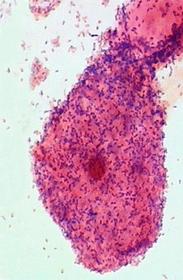

Which of the following best describes this Gram stain of a sputum specimen?

This image contains the following…

A) White blood cell(s)

B) Epithelial cell(s)

C) Gram-positive bacteria

D) All of the above